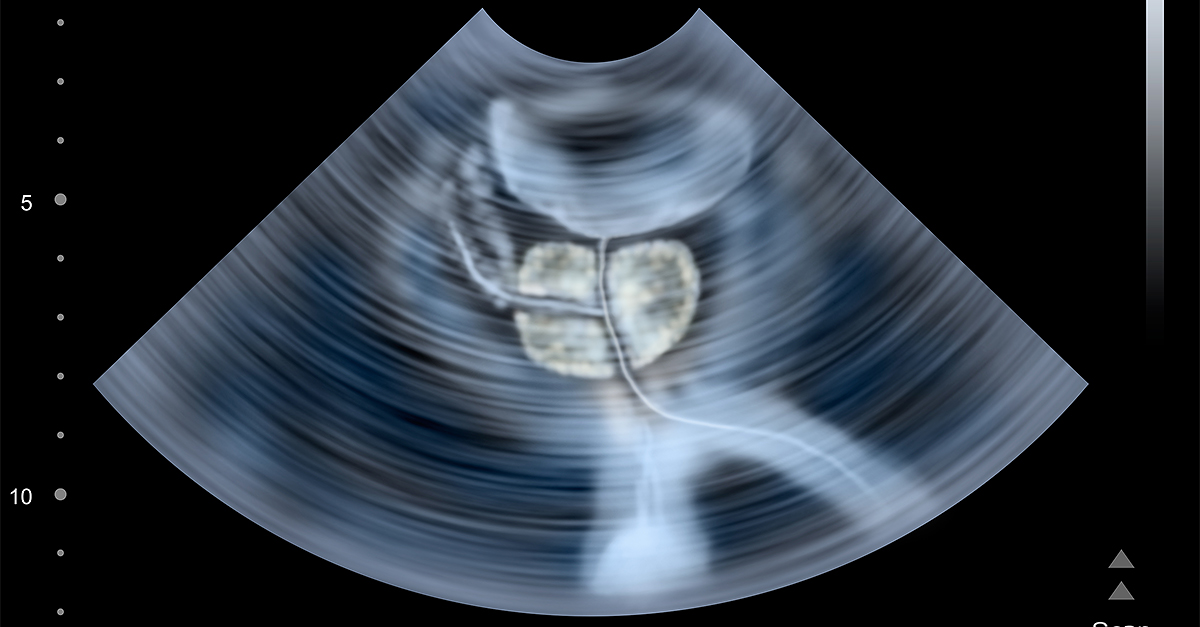

Kathrins pointed out the importance of a post-void residual (PVR) urine test, which measures the amount of urine left in the bladder. This indicates how well a man's bladder is emptying and whether he's retaining urine.

"If that residual starts to drift up and it reaches this red zone, as a urologist, you start to pay attention," he said. "If he's bothered already, I worry about his bladder getting exhausted, and I would push him to intervention."

If the bladder is functioning well and urine is emptying, the risk of the patient progressing to needing a catheter in the future is relatively low, Kathrins added, and intervention would typically not be necessary.